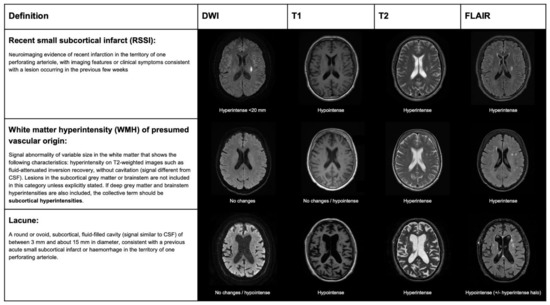

- Wardlaw, J.M.; Smith, E.E.; Biessels, G.J.; Cordonnier, C.; Fazekas, F.; Frayne, R.; Lindley, R.I.; O’Brien, J.T.; Barkhof, F.; Benavente, O.R.; et al. Neuroimaging Standards for Research into Small Vessel Disease and Its Contribution to Ageing and Neurodegeneration. Lancet Neurol. 2013, 12, 822–838. [Google Scholar] [CrossRef]